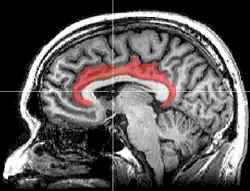

Gyrus cinguli

Der Gyrus cinguli[1] (von lateinisch gyrus ‚Windung‘ und cingulum ‚Gürtel‘) oder Gürtelwindung ist ein Teil des Gehirns und gehört funktionell zum limbischen System. Es handelt sich um eine Struktur des Telencephalons (Endhirn), oberhalb des Corpus callosum (Balken), die die medial liegenden Teile der Hemisphären miteinander verbindet.